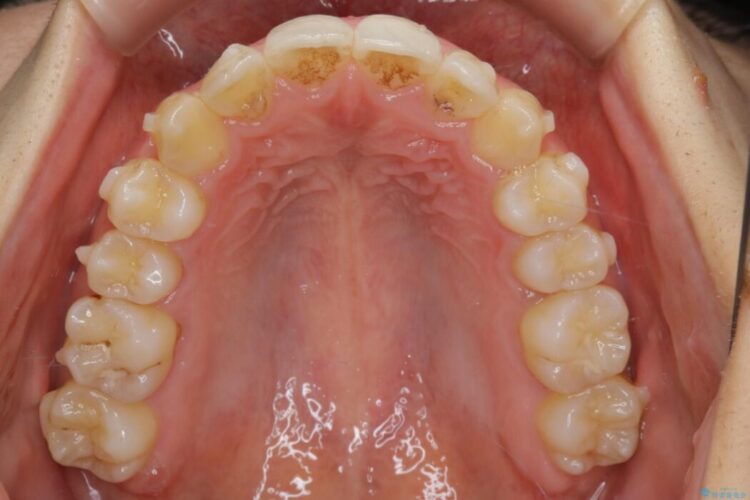

検査したところ叢生度合いから抜歯をせずとも治療が可能と判断しましたので、インビザラインでの非抜歯矯正を行う方針としました。

治療後写真を見ても歪みが解消され、歯列弓がきれいに整ったのが分かると思います。インビザラインをしっかりと装着されていたこともあり、矯正としては短期間の治療となりました。